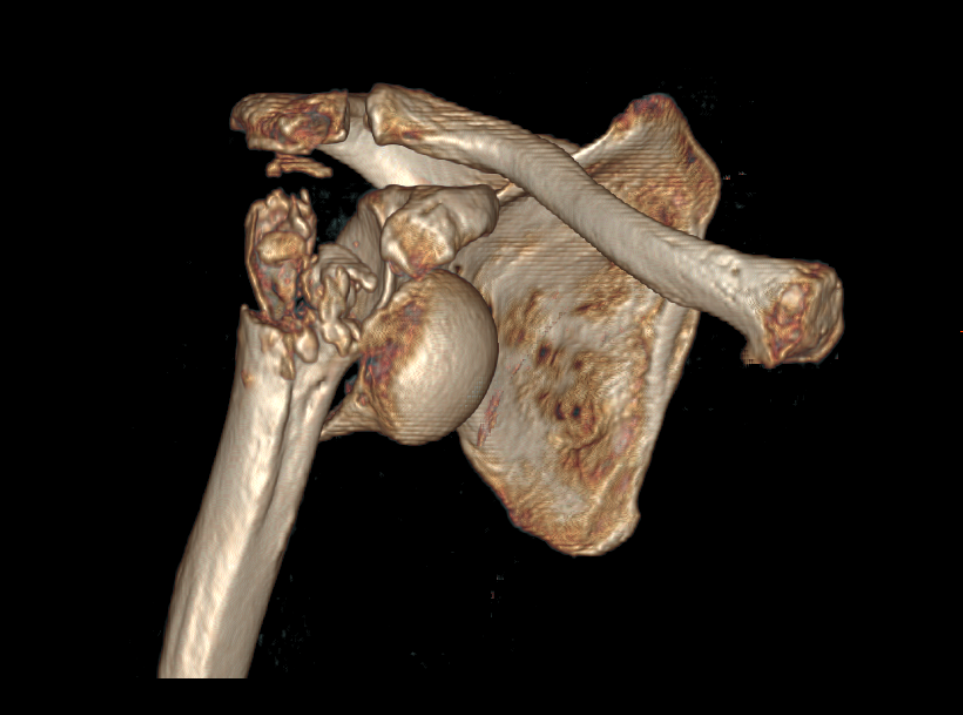

患者魏先生(化名)72岁,因晨练时摔倒致右肩肿痛、活动受限一天后入院,诊断为右肱骨近端粉碎性骨折伴肩关节脱位,骨科会诊后建议手术治疗。考虑到患者右肱骨近端四部分骨折、高龄及骨质疏松症等,采用常规的钢板内固定手术失败率极高,经骨科专家团队姜为民主任、林俊主任及王亮副主任的全面评估、讨论,决定采用反式肩关节置换术,以期重建关节稳定性及活动功能。

术前CT重建示右肱骨头及大小结节粉碎性骨折伴关节脱位